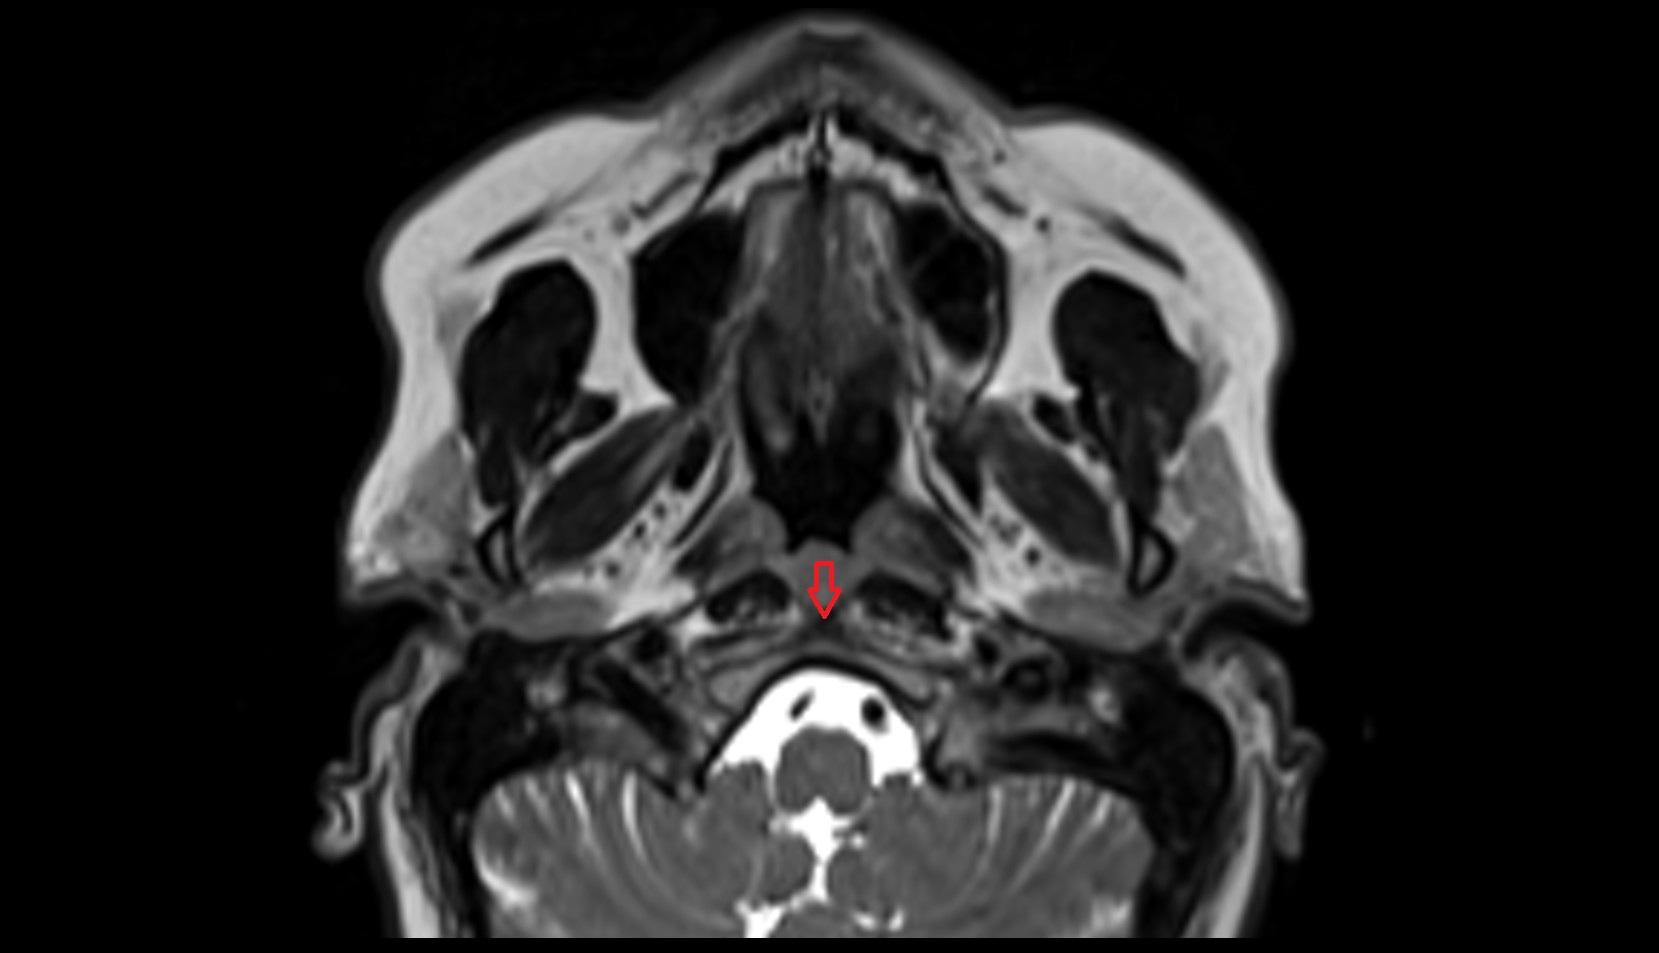

- Optic chiasm